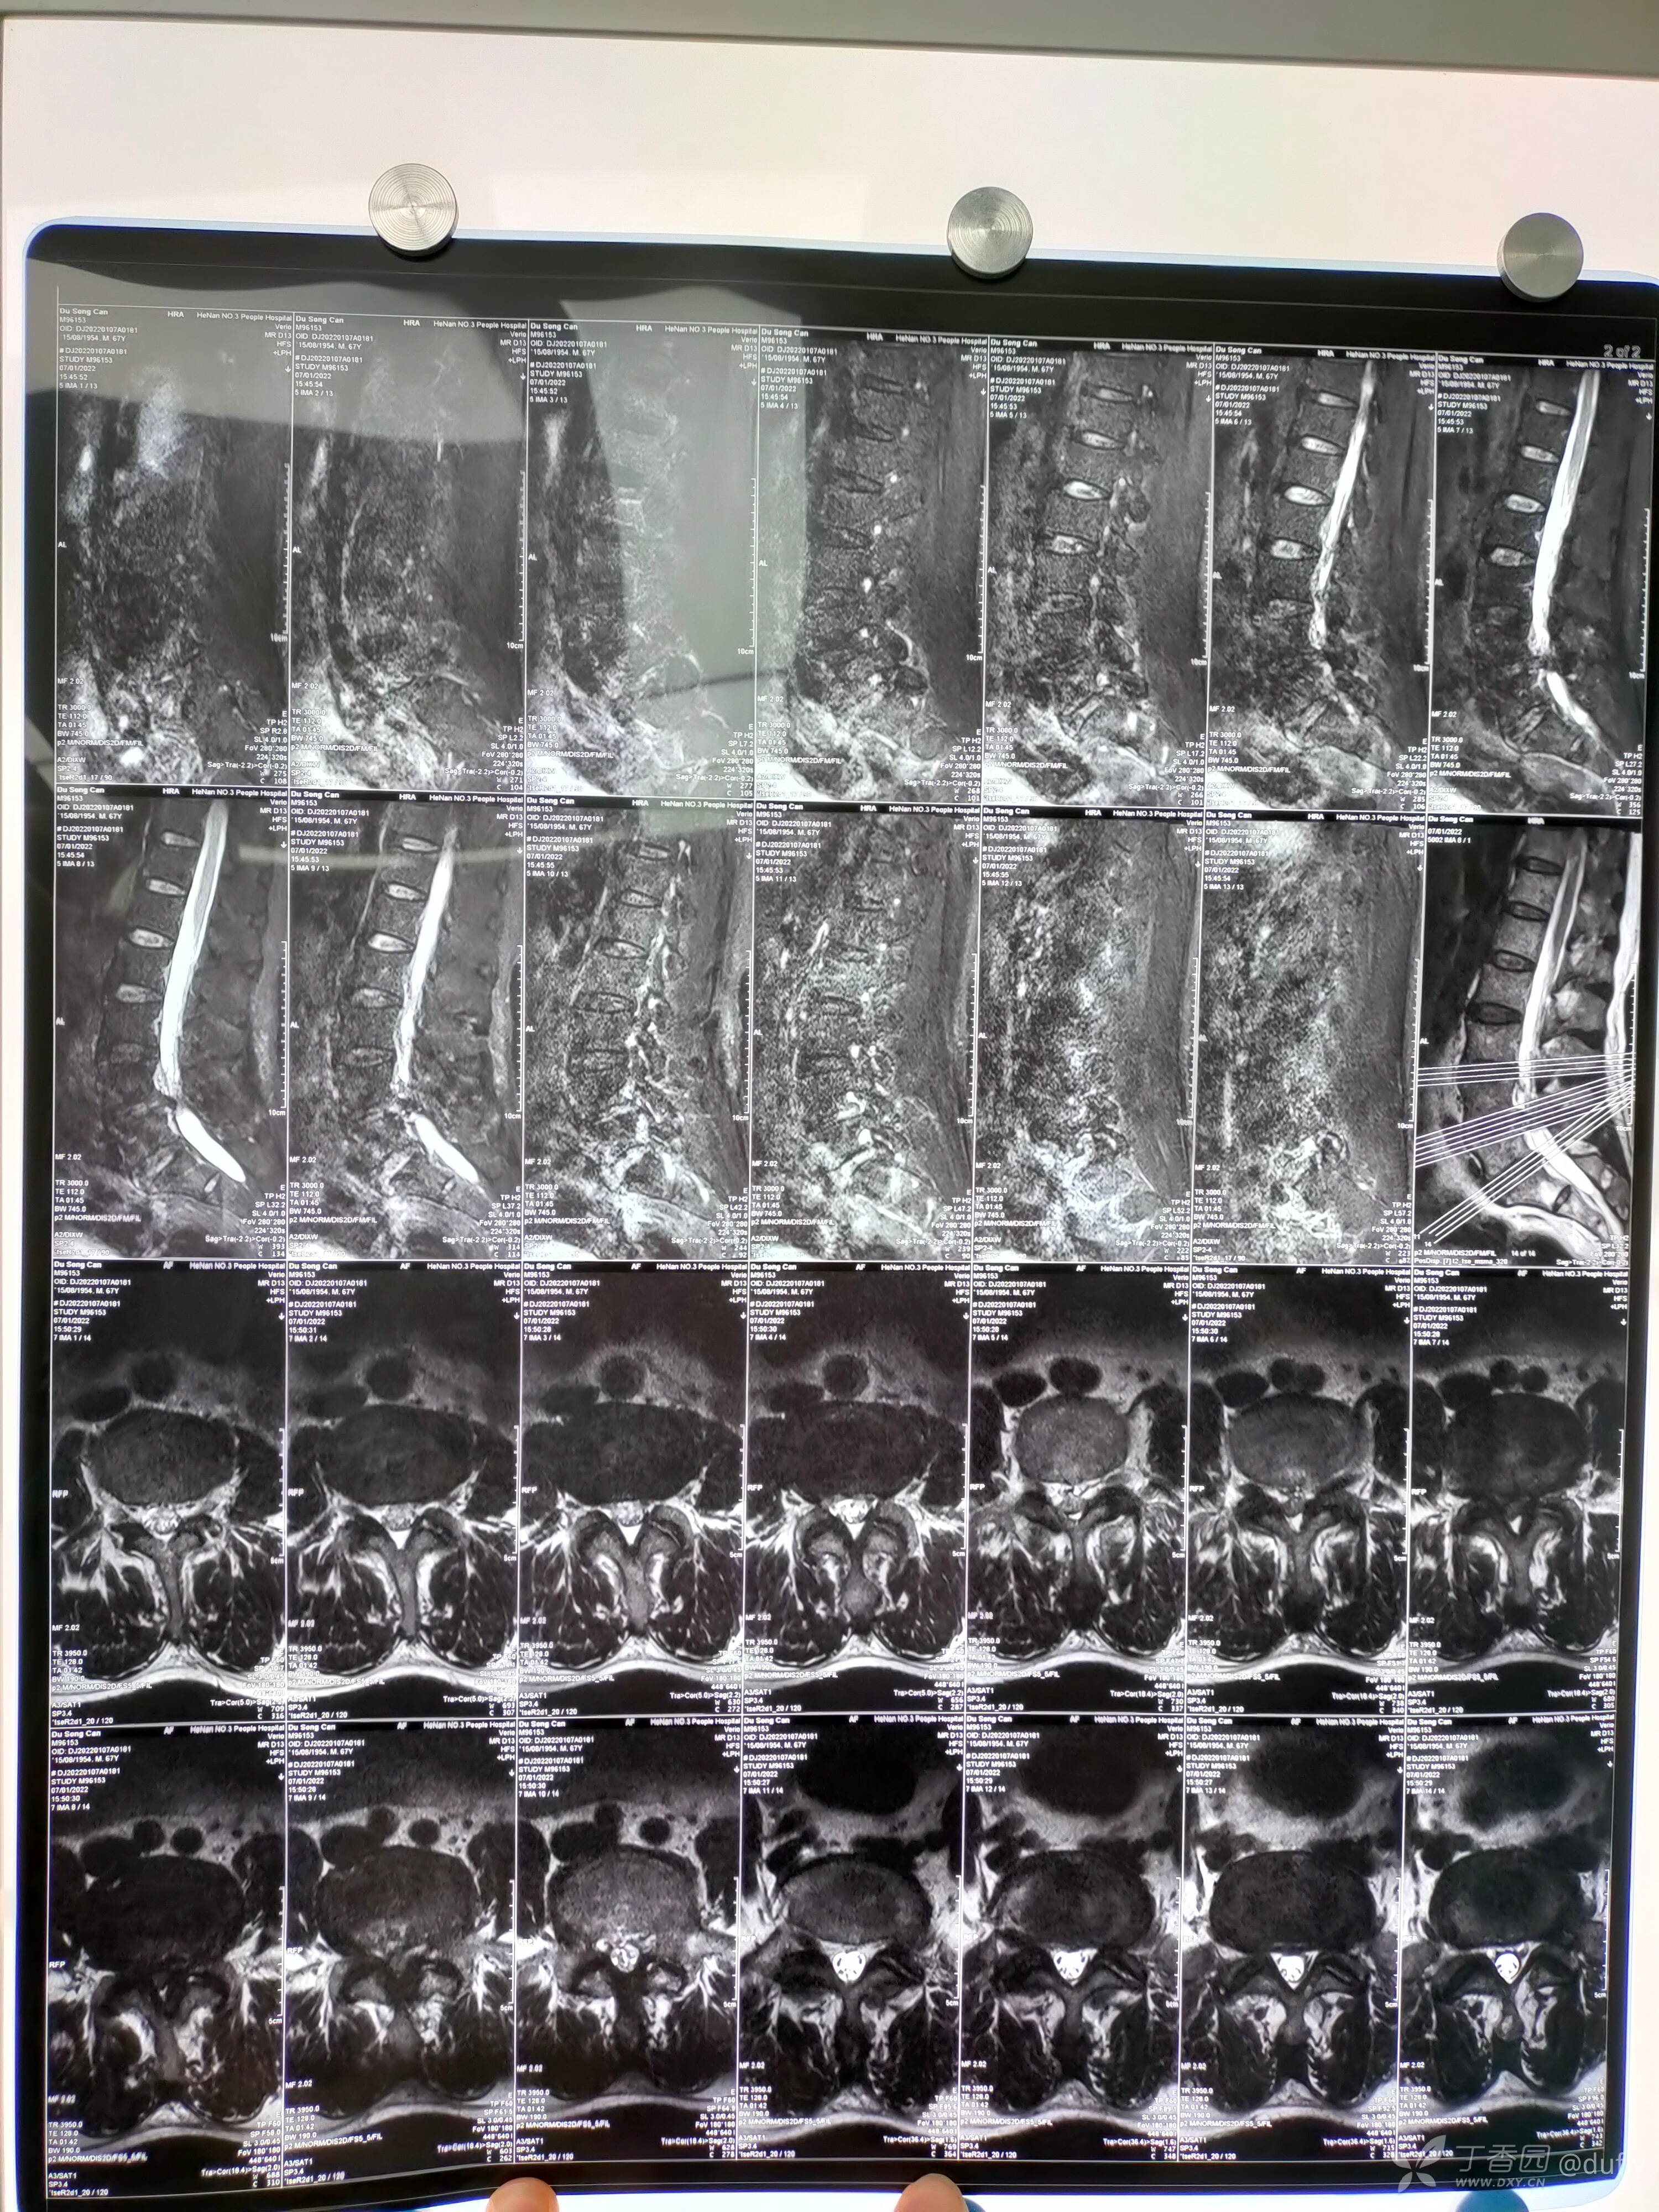

腰椎核磁:腰45重度椎管狭窄。腰5骶1左侧极外侧突出。

初步诊断:腰椎管狭窄症(L4/5),腰椎间盘突出症(L5/S1,左侧,极外侧)。